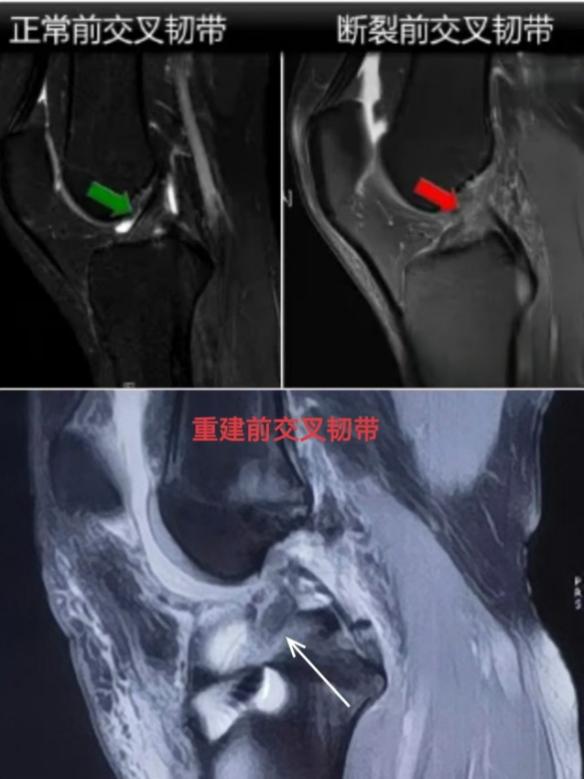

膝关节前、后交叉韧带损伤多见部分撕裂,严重的可出现完全断裂,一旦损伤,很难自愈。传统治疗方法通常是取自体股薄肌、半腱肌两根肌腱,通过股骨侧悬吊固定、胫骨侧挤压钉固定,此方法创伤较大且存在术后骨道增宽风险,恢复时间长。考虑到实际情况,骨伤二科医疗团队决定为何同学实施“关节镜下前交叉韧带断裂人工韧带重建手术”。

骨伤二科主任汪绪芳介绍:人工韧带可以用于人体各部位韧带、肌腱损伤的手术治疗。就最常见的膝关节前交叉韧带断裂而言,必须通过手术重建韧带才能重返运动。传统的取自体肌腱手术方案创伤大,恢复慢,术后至少恢复10个月才能重返运动。如果使用人工韧带进行韧带重建,最快3个月就能重返竞技比赛,人工韧带的术后恢复速度是自体肌腱的4倍,对于职业运动员和运动爱好者来说意义重大。